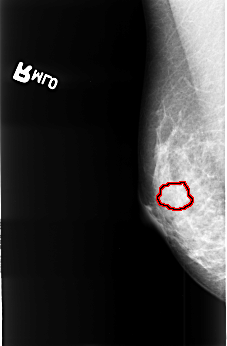

B_3403_1.RIGHT_MLO

FILE: B_3403_1.RIGHT_MLO.OVERLAY

TOTAL_ABNORMALITIES 1

ABNORMALITY 1

LESION_TYPE MASS SHAPE IRREGULAR MARGINS OBSCURED-ILL_DEFINED

ASSESSMENT 3

SUBTLETY 1

PATHOLOGY MALIGNANT

TOTAL_OUTLINES 1

BOUNDARY